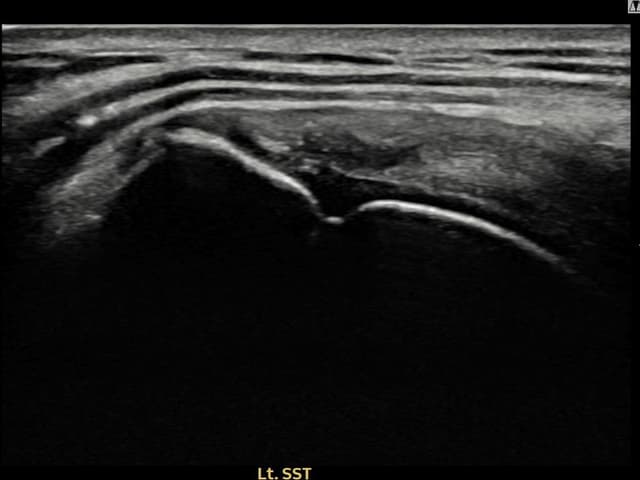

[촬영시기:22.10.06~22.11.14]

[어깨인대 축소봉합술] 좌측 어깨 극상근건 광범위 파열로 수개월간 일상생활이 어렵던 중 내원하셨습니다.